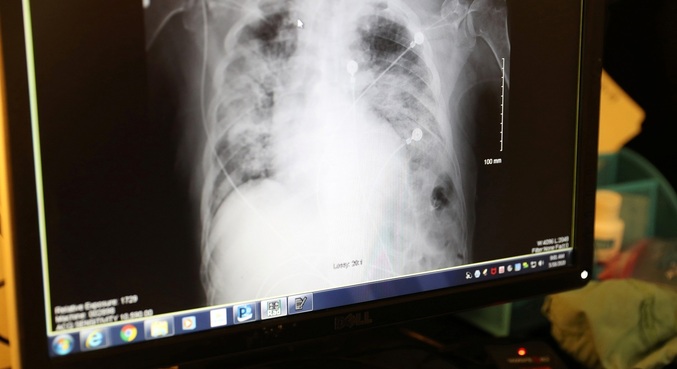

Exame de imagem mostra pulmão de paciente de covid-19 comprometido

Exame de imagem mostra pulmão de paciente de covid-19 comprometido Lucy Nicholson - 18.mai.2020/Reuters